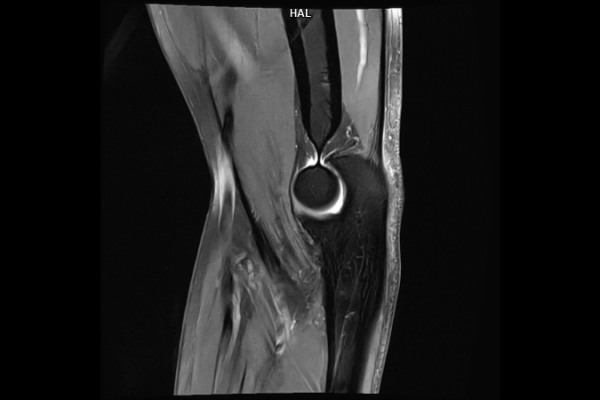

Detailbild MRT

• Muskuloskelettale Bildgebung

Wir bieten ein breites Spektrum an Untersuchungen an, von Standarduntersuchungen der Gelenke, Organe oder großflächigen Körperregionen bis zu Spezialuntersuchungen zum Beispiel des Herzen oder der Gefäße. Zusätzlich werden Angiographien (Darstellung von Blutgefäßen), Endometriose-Abklärungen und Mamma-Untersuchungen durchgeführt. Genauere Details können Sie der MRT/CT-Übersicht und der Preisliste entnehmen, oder Sie wenden sich direkt an unser Team, das Sie gerne zur passenden Untersuchung berät.

Die MRT (Magnetresonanztomographie) arbeitet mit Magnetfeldern und Radiowellen und eignet sich besonders für Untersuchungen der Weichteile wie Gehirn, Muskeln oder Gelenke. Die CT (Computertomographie) nutzt Röntgenstrahlen und liefert schnelle, hochauflösende Bilder, insbesondere für Knochen, Lunge oder innere Organe. Die Wahl der jeweiligen Untersuchung richtet sich an das individuelle Krankheitsbild und wird bei der Überweisung festgelegt.